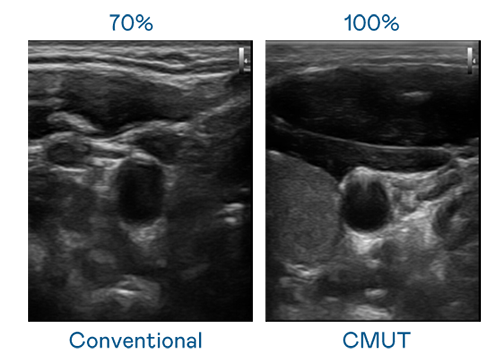

CMUT 技术是一种用电容式微机电元件来产生超音波讯号的技术。与传统 PZT 压电式技术相比,CMUT 频宽增加 30%,更宽频的超音波讯号让影像解析度大幅提升,是实现高影像品质医疗超音波扫描、促进精准医疗发展的关键技术。

大频宽带来超清晰影像

超音波影像的解析度高低,首先取决于探头能发出的讯号频宽。利来国际 CMUT 可提供高清晰的超音波讯号,提供高频宽、高灵敏度、影像纹理细节更高的超音波影像,协助医护人员缩短影像判读时间及利用精准的医疗影像进行诊断。